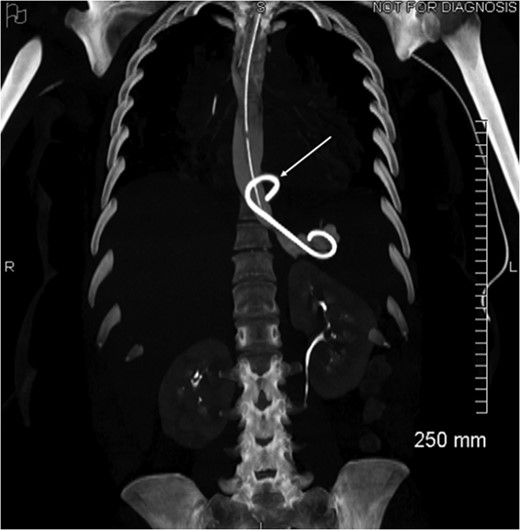

Proximal end of the double pigtail drain externalizes in the pericardium (arrow).

Coronal view of opacification on CT showing the externalization of the drain in the pericardium (arrow).